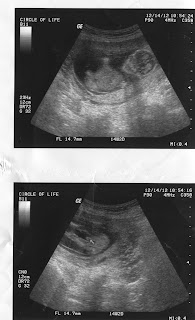

IT'S A BOY!!!!!!

At 13 1/2 wks we were able to find out what we were having! We are so EXCITED we are having a BOY!